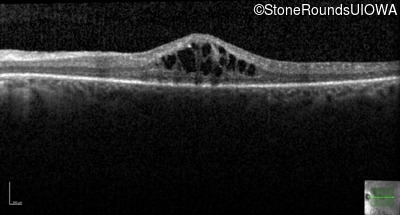

AR Retinitis Pigmentosa (IA1aiii)

Age at visit:

28 years

OD

OS

20/25

20/32 -2

Diagnosis & molecular findings

Disease

Gene

Allele 1 variant(s)

Allele 2 variant(s)

Inheritance mode

AR Retinitis Pigmentosa

ZNF408

His455Tyr CAT>TAT

Arg567Stop CGA>TGA

AR